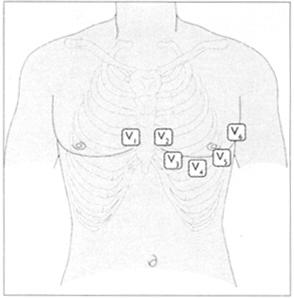

●肢导一般是水平的,如果不是就用表13所示的彩色电极。最好把电极放在无汗毛的区域,如前臂的内侧和腿的外侧,踝关节之上电极放置的位置见表14和图40。

表14 胸导联的位置

图40 胸导联的位置